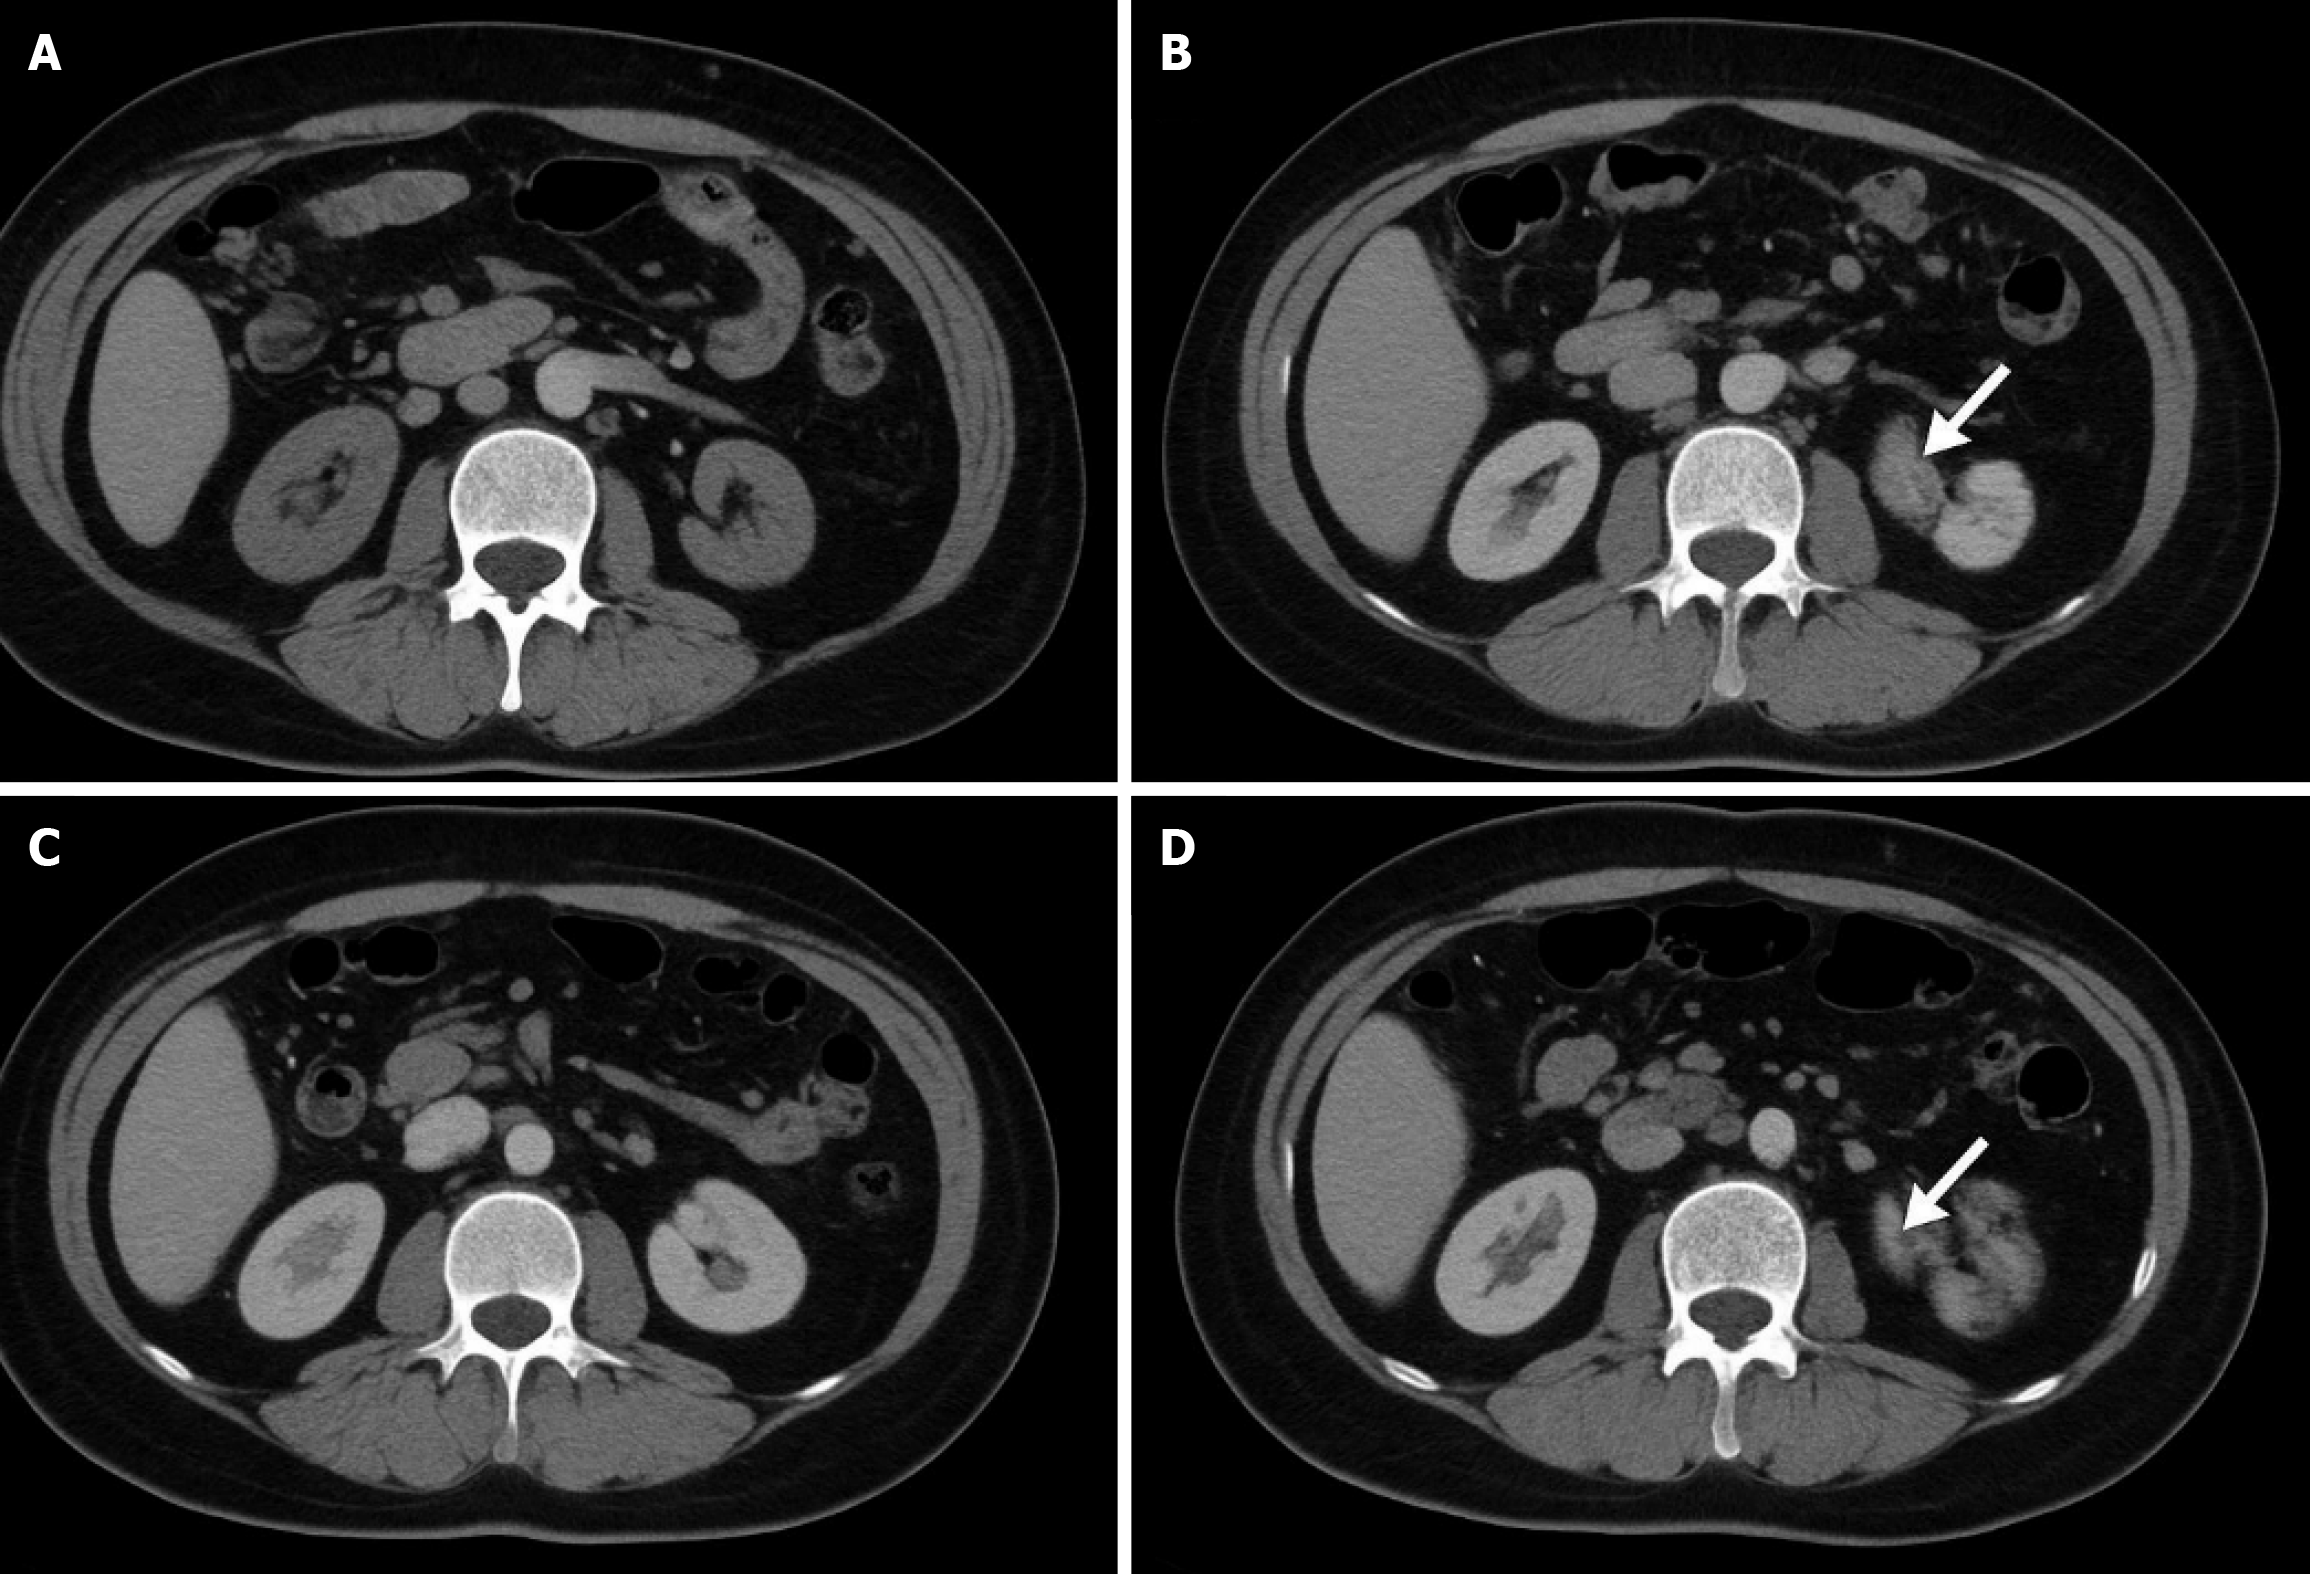

Figure 1 Imaging test of typical case.

A: Shows the image detection of the operation area of the abdominal obesity group on the 30th postoperative day (POD). The imaging performance of the abdominal operation area of the patient with abdominal obesity on POD 30 showed that the tissue structure in the operation area was clear and there was no abnormal density shadow or effusion. The wound healed well; B: Shows the imaging findings of local recurrence in the abdominal obesity group three months after surgery. Reexamination of the patient with abdominal obesity at 3 months after surgery showed an irregular soft tissue density shadow (arrow) at the edge of the original operation area, and the boundary was fuzzy, indicating local recurrence; C: Shows the image detection of the operation area of the non-abdominal obesity group on the 30th POD. The imaging performance of the patient with non-abdominal obesity in the operation area on POD 30 showed that the anatomical level of the operation area was clear, and no obvious exudation, hematoma, or recurrence was found; D: Shows the imaging detection of local recurrence at 3 months after surgery in the non-abdominal obesity group. The imaging detection figure of the non-abdominal obesity patient three months after operation shows that nodular abnormal signal shadow with a diameter of about 1.2 cm (arrow) appears in the adjacent area of the operation area, and the enhanced scan is uneven and intensive, suggesting local recurrence.